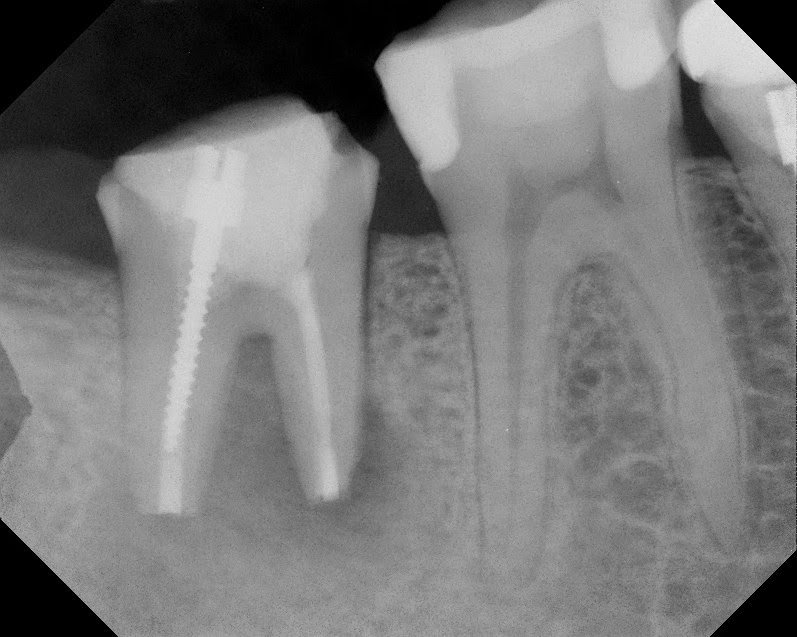

Previous posts have discussed the often overlooked surgical option of intentional replantation. The following case is an example of 3.5 yr success of intentional replantation of a Md second molar.

At this point, retreatment or surgery are the options to preserve the tooth. With a crown, not needing to be replaced, a long post and overfilled gutta percha – which can be difficult to retrieve, we considered a surgical approach. Since this is a second molar, the buccal bone is too thick to allow for conventional surgical approach (apicoectomy). After discussing risks of intentional replantation, pt elected to preserve tooth using intentional replantation.